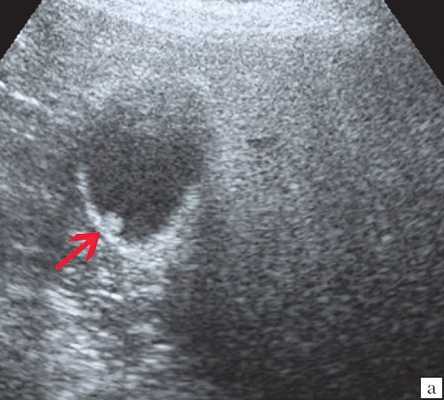

Клиническая картина желчнокаменной болезни многообразна [5-6, 10]. Условно выделяют хроническую болевую, хроническую рецидивирующую, диспептическую, стенокардитическую и ряд других клинических форм. Характерным ультразвуковым признаком конкремента в желчном пузыре является его акустическая тень. Такая тень возникает из-за высокой плотности камня по сравнению с мягкими тканями. Наличие или отсутствие тени помогает отличить камень от полипа желчного пузыря (рис. 4).

а) Одиночный конкремент желчного пузыря (подвижная гиперэхогенная структура, дающая четкую теневую дорожку).